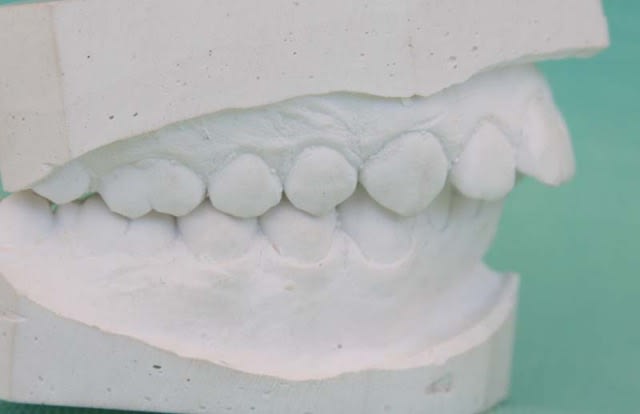

Modèles de départ@+ Bjc.

Moulage diagnostic 4 2 v4732a - Eugenol

1 p3qrc4 - Eugenol

Bjc.

20/07/2009 à 17h58

je ne peux pas changer de technicien pour la bonne raison que nous n'en avons pas

le plus proche est à 3 000 Km.

;-)))

voici une meilleure photo du coté D.

P.S.: ce n'est pas un beau modèle en plâtre qui fait un bon TTT.

Chére EloD.,

bien que mon modèle ne soit pas en taille américaine, tu as trouvé en quelle classe il est ?

ou plutôt, il était au départ